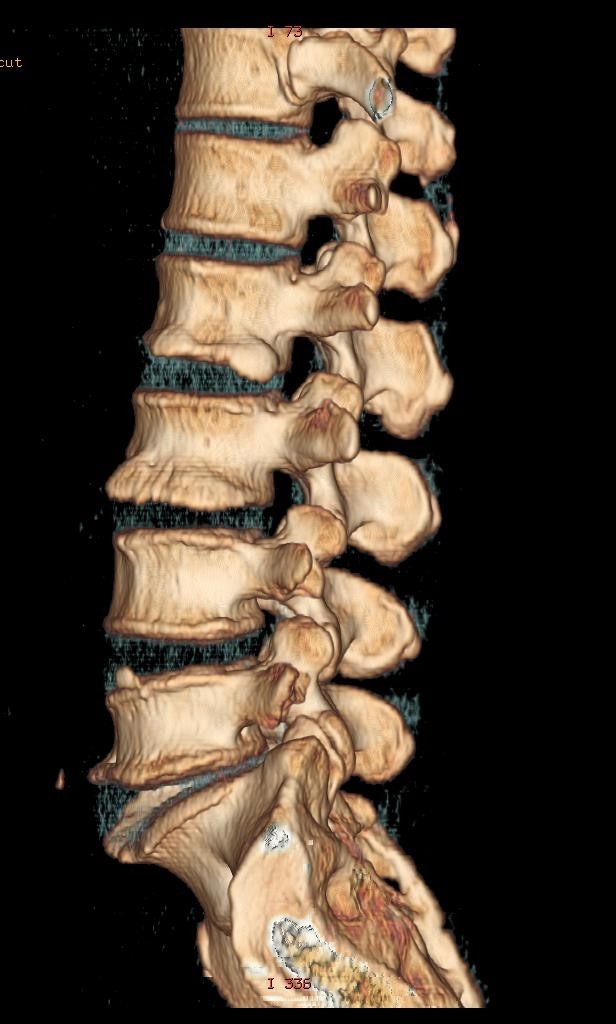

- 布骨医学科普: 浅谈腰椎间盘突出症 布骨康复医疗中心 ,2021-06-22

- 引起腰椎间盘突出症的原因有哪些?造成椎间盘突出症的基本原因是椎间盘退变。椎间盘退变可以是一种生理性过程,也可以由多种因素造成。导致椎间盘突出症的诱发因素尚未有明确的定论,年龄、性别、身高、体重、身体素质、外伤史、职业、吸烟、驾驶机动车引起的身体撞击、基因等均有可能成为诱发因素。腰椎间盘突出症是如何发.....

- 布骨医学科普:如果你还年轻,请照顾好你的椎间盘! 布骨康复医疗中心 ,2021-06-10

- 我曾经看到过一些关于腰痛知识普及的热门文章,他们很努力地想要向老百姓解释一个误区――椎间盘突出不等于椎间盘突出症,那篇文章是基于这么一个现状,很多人去医院看局部腰痛,并没有明显的下肢放射性疼痛,医生做了很多检查都没有发现明显的器质性问题,但是患者腰痛客观存在,所以就把影像学上的椎间盘突出变性当作患者.....